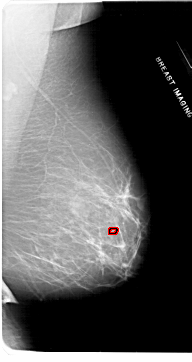

A_1953_1.RIGHT_CC

RIGHT_CC LINES 6616 PIXELS_PER_LINE 3436 BITS_PER_PIXEL 12 RESOLUTION 43.5 OVERLAY

FILE: A_1953_1.RIGHT_CC.OVERLAY

TOTAL_ABNORMALITIES 1

ABNORMALITY 1

LESION_TYPE CALCIFICATION TYPE PLEOMORPHIC DISTRIBUTION CLUSTERED

ASSESSMENT 4

SUBTLETY 1

PATHOLOGY BENIGN

TOTAL_OUTLINES 1

BOUNDARY